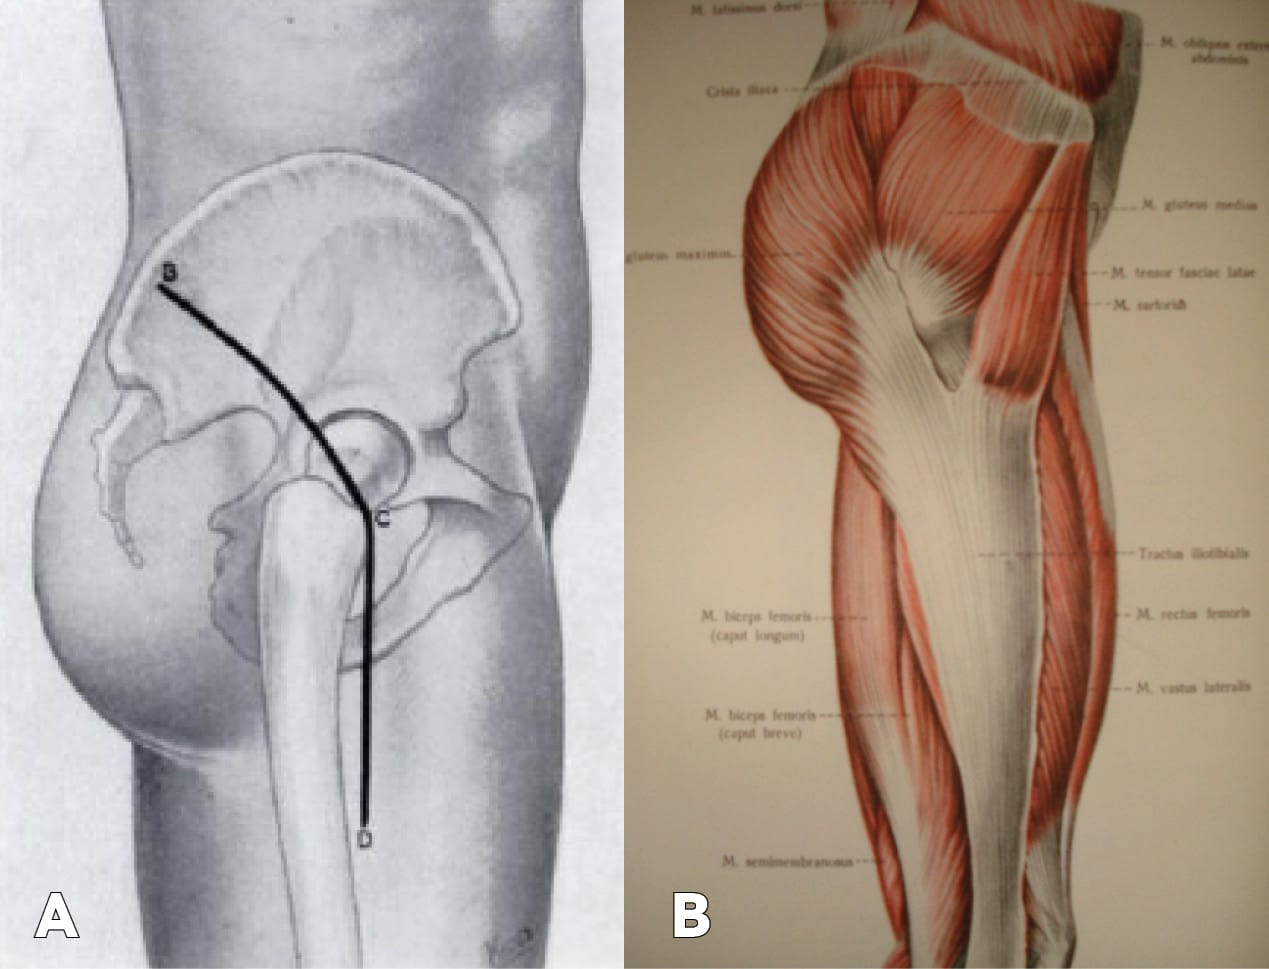

The surgical approach was as follows: After tightly filling the fistulous tract with a solution of green dye and hydrogen peroxide along the posterolateral surface of the lower third of the right femur just below the greater trochanter, a skin incision approximately 12 cm in length was made (Figure 2 A).

The subcutaneous fat tissue was separated and the fascia lata of the thigh was exposed. A cavity stained with green dye was found in the area of the lateral surface of the thigh. The fistulous tract extended between the m. tensor fasciae latae and the tendinous part of the m. gluteus maximus to the posterior surface of the femur. A fascial incision was made at the junction of the gluteus maximus and the fascia lata, transitioning into the iliotibial tract directed toward the posterior surface of the femur (Figure 2 B). The limb was rotated inward. During wound revision, a fistulous tract was found, extending along the upper edge of the m. quadratus femoris to the lesser trochanter. The m. quadratus femoris was bluntly separated from its attachment to the femur, and the lesser trochanter was exposed in the wound (Figure 3).

In the literature available to us, we found surgical approaches to the lesser trochanter used in tumors in this area. The approach was performed from the anterior-medial surface (1971) [1] Zatsepin ST, Gamidov EM. Tumors of the lesser trochanter and their surgical treatment. Orthop Traumatol Prost. 1971 May;32(5):33-5.. R.E. Zhitnitsky (1976) [2] Zhitnitskiĭ RE. Choice of approach for surgical treatment of tumors in the region of the lesser trochanter and posterior-inferior surface of the femoral neck. Orthop Traumatol Prost. 1976 Nov;(11):40-1. described the Gibson approach for surgical treatment of tumors in the region of the lesser trochanter and the posteroinferior surface of the femoral neck. In this approach, access to the lesser trochanter is through the distal part of the Gibson approach. The A. Gibson surgical approach is a modification of Kocher’s approach, published by him in 1950 [3] Alexander Gibson. Posterior Exposure of the Hip Joint. J Bone Joint Surg 1950;32B:183-186.. The skin incision for this approach begins at the posterior superior iliac spine and the anterior angle of the greater trochanter. The author then describes the now well-known sequential approach to the hip joint, without mentioning anything about the lesser trochanter. This approach to the hip joint was also described by V.D. Chaklin in 1964 [4] Chaklin V.D. Basics of operative orthopedics and traumatology. Moscow, 1964, p. 737. . Amr S. (1998) described a modification of the A. Gibson approach, but this modification also related to access to the hip joint [5] Amr S. Transverse subgluteal-ilioinguinal approach to the acetabulum. Microsurgery. 1998;18(7):432-41..

The approach we used is indicated by arrows and passes, bypassing the main muscle groups of the thigh and neurovascular bundles. Particular caution is required when separating the m. quadratus femoris from the femur, as the sciatic nerve runs immediately behind it.

On the other hand, this is a surgical approach to the lesser trochanter that can be considered a modification of the A. Gibson approach and allowed for atraumatic resection of the lesser trochanter and debridement of this area.